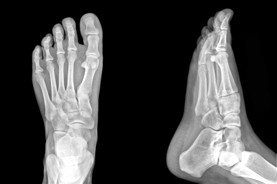

The Foot Institute is an association of Calgary Doctors specializing in the medical treatment of the foot and ankle, and is one of the largest groups of foot specialists in Alberta.

The Calgary Foot Institute is dedicated to the medical and surgical treatment of the foot. Our mandate is to provide the best possible medical, surgical and preventative treatment available for our patients. We do this by providing well-trained Doctors who are committed to treat and prevent all types of foot pain, biomechanical disorders, as well as all other problems relating to the feet.

At the Calgary Foot Institute, our Doctors are trained to specifically treat problems associated with your feet or ankles. Below are several of the most common problems that we see on a day to day basis: